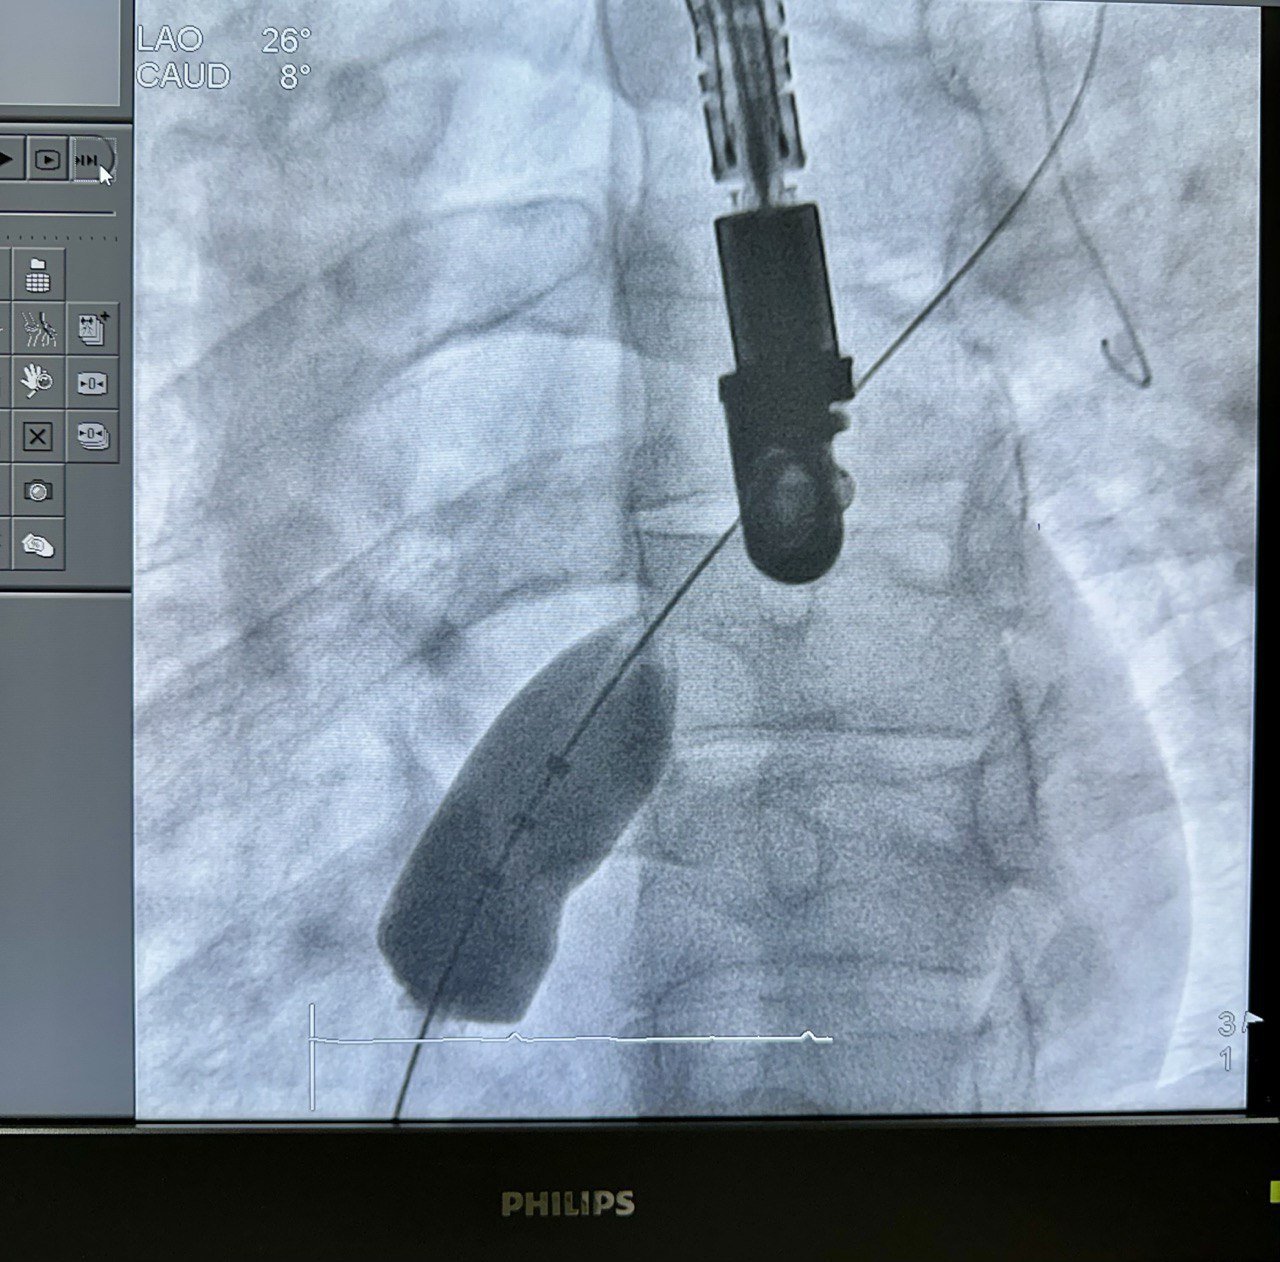

Замість відкритого хірургічного втручання лікарі застосували малоінвазивний ендоваскулярний метод.

Через судину пацієнту ввели спеціальний пристрій — оклюдер, який закрив дефект та відновив нормальний кровообіг. Операція пройшла без розрізів, без зупинки серця та без застосування штучного кровообігу.

У цій операції були задіяні ендоваскулярний хірург Ігор Дітківський і лікар-анестезіолог Юлія Єрмолович.